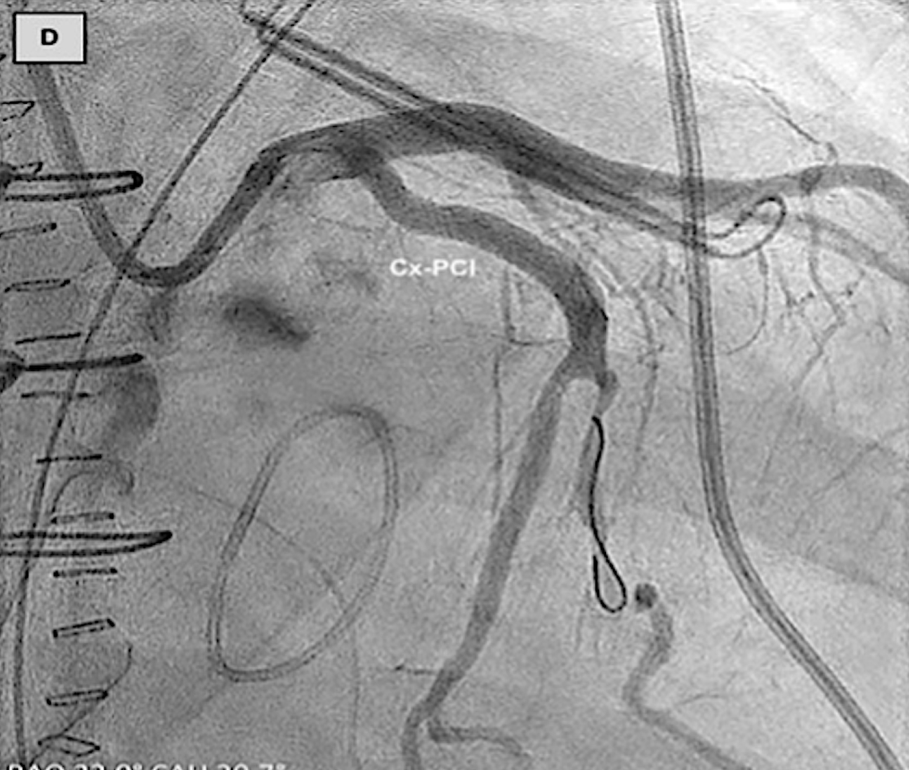

(A)使用Amplatzer装置的左心耳封堵术已完全展开。冠状动脉造影证实,在植入后,回旋支-M1冠状动脉存在明显狭窄。(B)回旋支-经皮冠状动脉介入治疗

临床病例报告也证实了该损伤的可干预性:一例59岁患者行Amulet装置左心耳封堵时,因装置压迫导致LCX近端重度狭窄,出现下壁ST段抬高,重新将装置深入左心耳开口并联合LCX-PCI后,狭窄完全解除;另一例患者行二尖瓣、三尖瓣手术联合AtriClip装置左心耳封堵后24小时,因装置压迫导致LCX闭塞引发心肌梗死,经LCX-PCI后狭窄显著改善。